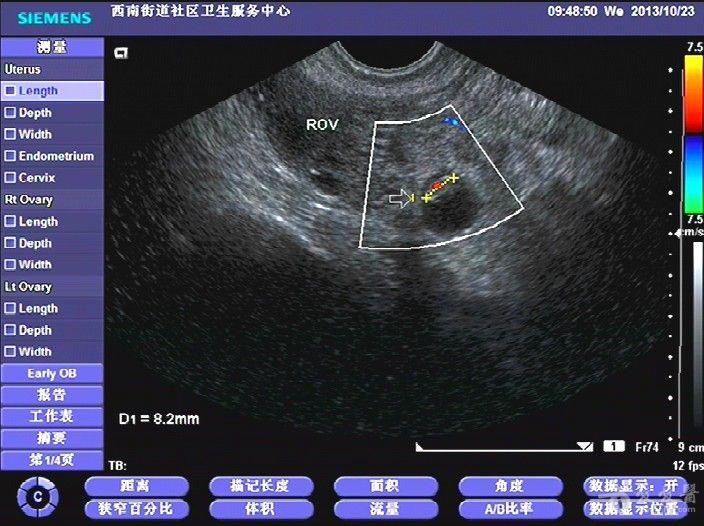

超声所见:子宫稍大,宫内可见一小囊(假孕囊),右侧输卵管见明显孕囊,囊